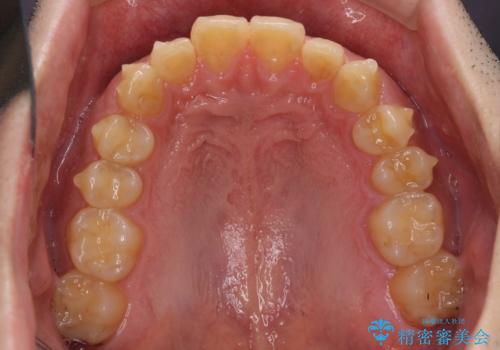

- 上下前歯のデコボコと下の前歯が隠れるほどの深い咬み合わせを気にして来院された患者様です。

インビザラインによる上下歯列の拡大と、IPR(歯と歯の間を削る)にるスペースの獲得により、口元のデコボコとディープバイトを改善することとしました。

デコボコがなくなったことで日頃の清掃が行いやすくなり、深い咬み合わせが改善したことで、食いしばりによる顎の負担も軽減されました。